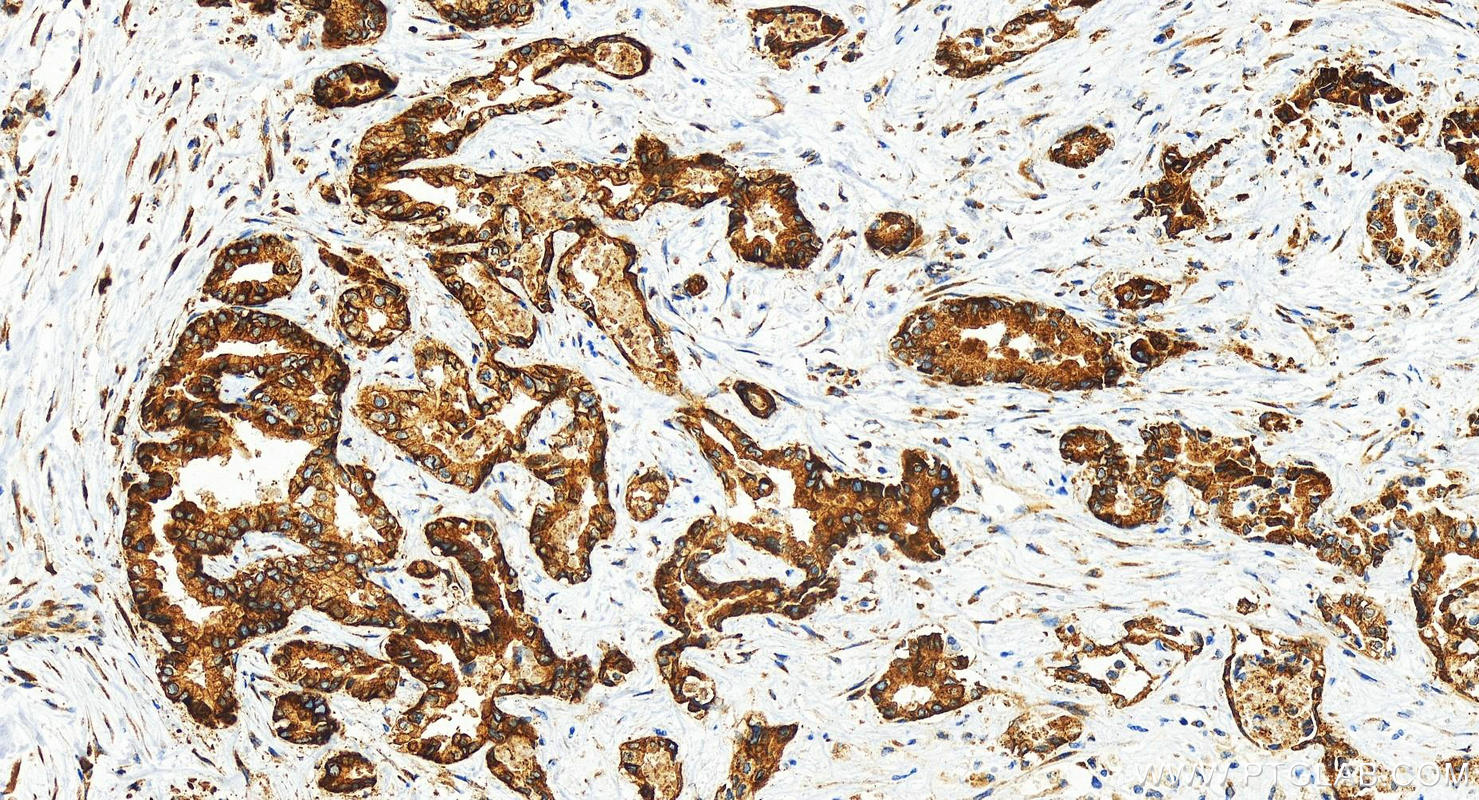

| Positive IHC detected in | human intrahepatic cholangiocarcinoma tissue Note: suggested antigen retrieval with TE buffer pH 9.0; (*) Alternatively, antigen retrieval may be performed with citrate buffer pH 6.0 |

| Immunohistochemistry (IHC) | IHC : 1:500-1:2000 |